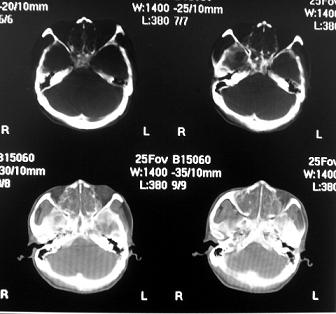

标题: CT10521:男。32岁,副鼻窦ct,请会诊。 [打印本页]

标题: CT10521:男。32岁,副鼻窦ct,请会诊。

男。32岁,鼻塞,流涕一年余。

好奇怪的 定位相

这是我第一见的

软组织密度影填满上颌蚪 筛窦及鼻腔,并导致筛骨 上颌窦内侧壁明显骨质破坏。多考虑:内翻性乳头状瘤!

鼻窦炎伴息肉形成可能,上颌窦内侧壁明显骨质破坏并无挤压,膨胀改变,多不考虑内翻性乳头状瘤.

骨板增生增厚,支持考虑炎症伴息肉,不排除肉翻乳头状瘤

双侧鼻腔内低密度软组织影,骨壁无明显破坏,鼻腔无扩大,双侧上颌窦、筛窦软组织影,窦壁增厚,结合临床考虑鼻息肉合并慢性上颌窦炎。